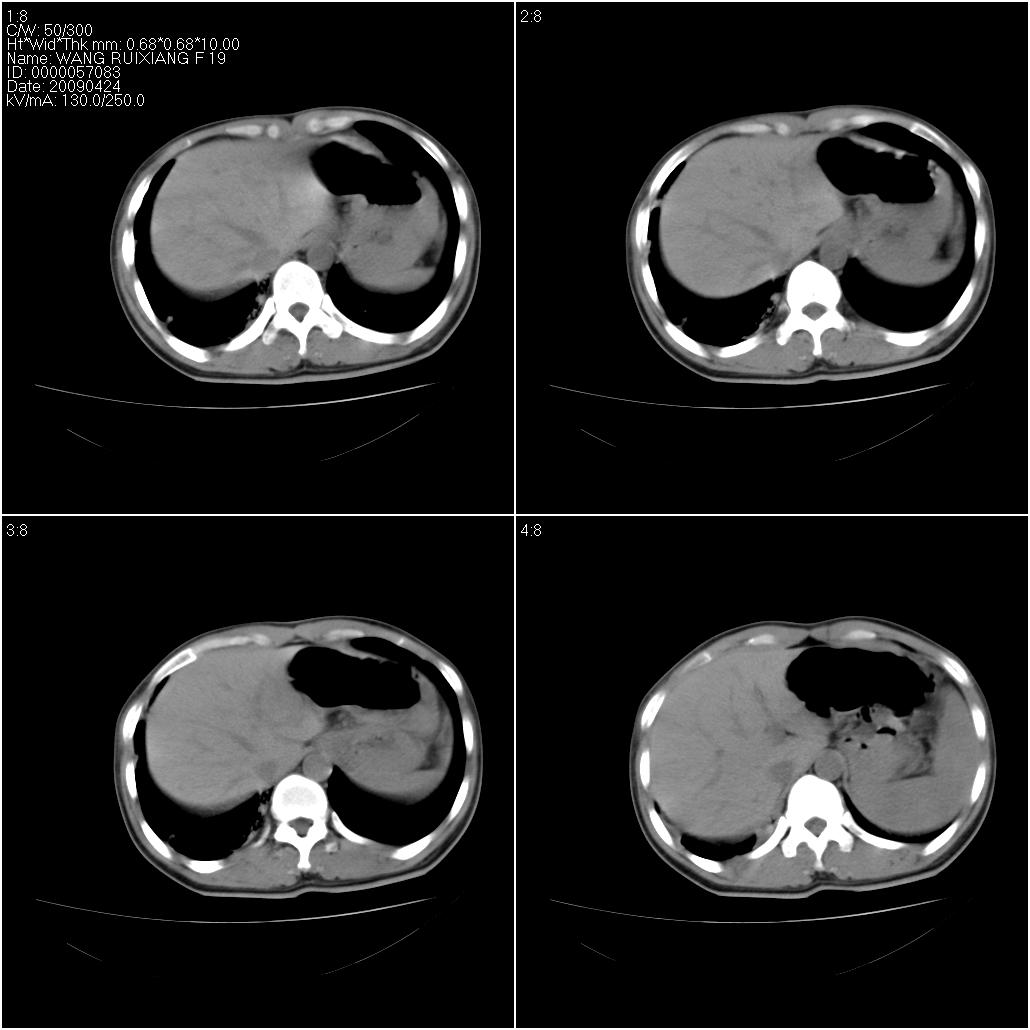

标题: CT19588:女性,39岁。患者胸闷不适,上楼时气喘。 [打印本页]

标题: CT19588:女性,39岁。患者胸闷不适,上楼时气喘。

片子上的年龄为19岁,是操作错误。该患者于去年5月份曾做平片和ct扫描,和这一次的ct检查没有明显变化。当时诊断为肺结核,进行抗痨治疗至今,但没有改善。呼吸功能试验为混合型呼吸困难。除此之外,该患者没有其他方面没有的临床症状和体征

间质炎伴肺气肿,支气管扩张